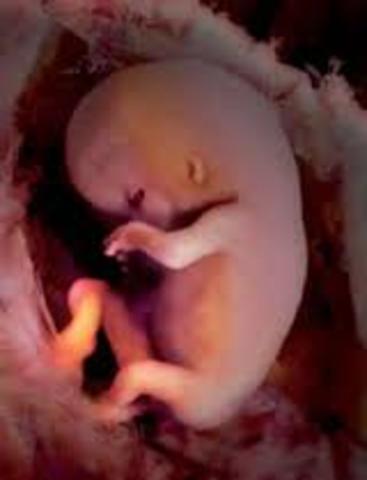

• (8-9 semanas) :

(8-9 semanas) :

Al final de la semana 8 ., el cuerpo esterar formando ., así como todos sus órganos y terminara el periodo embrionario

Dejara de ser embrión para convertirse en feto ., en esta semana crese los dedos de las manos y de los pies ., la cabeza es desproporcionalmente grande y se construye la mitad del embrión